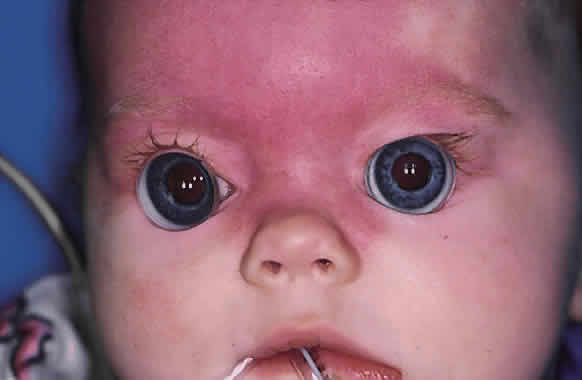

Funduscopy is essential, with both a direct and an indirect ophthalmoscope. The Richardson or Koeppe diagnostic gonioscopy lenses can be of great assistance (Fig. 3). The lens is placed, and then direct ophthalmoscopy is performed through the lens. After this, the periphery should be carefully evaluated with an indirect ophthalmoscope.

Gonioscopy is a mandatory part of the examination under anesthesia. It allows the surgeon to identify the underlying congenital or juvenile glaucoma diagnosis and permits appropriate surgical planning. The Koeppe gonioscopic lens, introduced in 1919,26 has significant advantages over the Zeiss four-mirror or Goldmann three-mirror gonioprism. Chief among these is the ability to compare simultaneously the gonioscopic appearance of two eyes in the same patient (see Fig. 3). The surgeon should be familiar with the gonioscopic findings in primary congenital glaucoma as well as the various secondary glaucomas seen in childhood. Gonioscopic photography can help document the appearance of the anterior chamber angle before and after treatment.